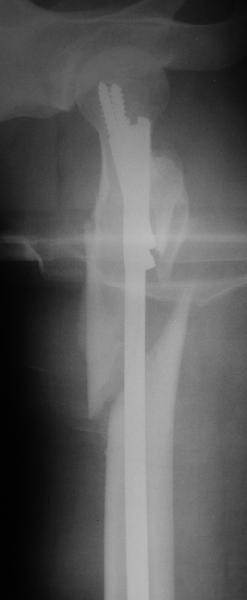

Оперировали вчера. Не сказать, что все прошло гладко - вертельная область была расколота и в сагиттальной, и во фронтальной плоскости, гвоздь попал в перелом и сместился кзади, что заметили уже после введения винтов, пришлось все извлечь и переставить. Снимки в приложении. Буду признателен за комментарии.

Если честно, мне не нравится стояние отломков

проксимального отдела. На мой взгляд причина в недостаточной осевой тракции сегмента перед этапом дистального блокирования. Если это действительно так, я бы попробовалудалить дистальные блокирующие винты, дать осевую тракцию(дистрактор, ортопедический стол, др.) и повторное дистальное

блокирование.

уважаемый А.Ч.! Не уверен, что отломки сопоставлены хорошо. Особенно плохо лбстоят дела с малым вертелом. Клинический исход по-видимому будет неудовлетворительным.

Похоже, не дотянули мы длину около 1 см - будем надеяться, что с учетом тяжелого перелома пятки на этой же стороне и перелома таза не это станет доминирующей проблемой. У пациентки скоро 2 месяца после операции, надеюсь, появится - сделаем снимки, глянем. Насчет несопоставления малого вертела - пожалуйста, поясните, какими бедами это чревато.